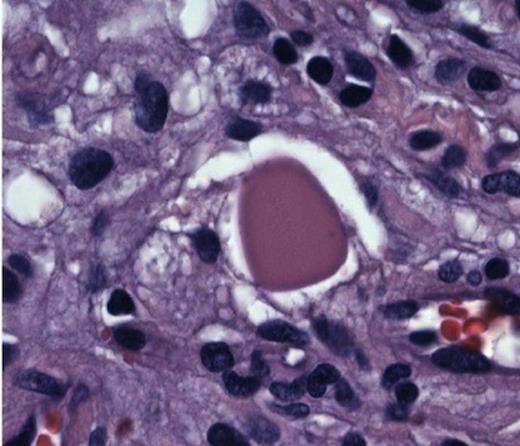

She was taken to the operating the following morning for a bicoronal craniotomy for a gross-total tumor resection with neuronavigation (Fig 2). Pathology was a dural-based WHO Grade 1 supratentorial haemangioblastoma. Microscopic findings demonstrated large vessels and abundant capillary networks, with a cellular proliferation of large stromal cells with clear vacuolated cytoplasm (Fig 3,4,5). There were significant hyperchromatic nuclei and multiple areas of PAS positive pinkish globules (Fig 3,4,5).

CD 34 positive staining of vascular lining consistent with haemangioblastoma

No mitoses were identified. No whorls or psammoma bodies were identified. Immunohistochemical findings showed interstitial tumor cells immunoreactive for NSE, factor X111A, and S100. RCC, EMA, Inhibin, GFAP, CAM 5.2, CD 10, and CD 34 were negative on the interstitial cells. CD 34 was positive on the vascular endothelium (Fig 3,4,5). She was discharged home within six post-operative days. She returned to clinic one week later and had no neurological deficits.

Hyperchromatic nuclei and typical Periodic Acid Schiff + globules at 100x